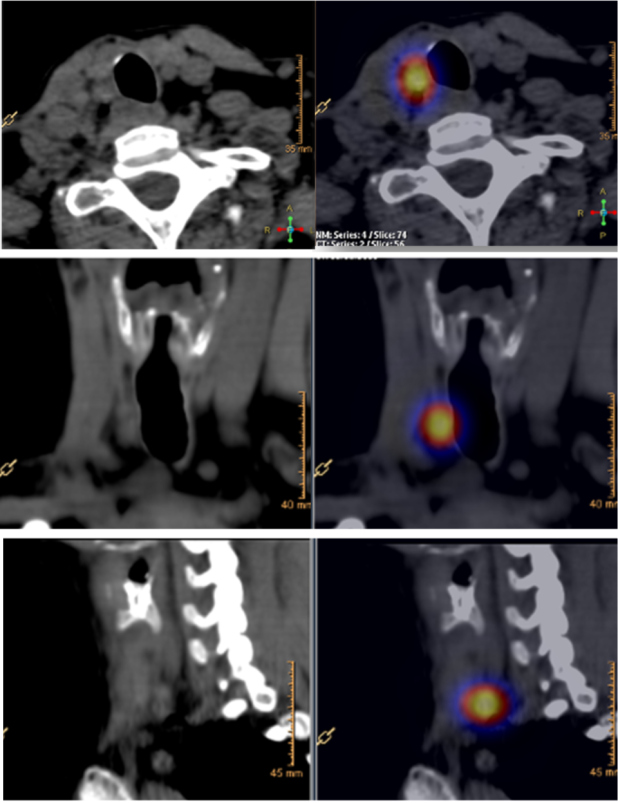

Procedimiento AMESPECT

Los pasos a seguir para completar el procedimiento son los siguientes (fig. 1):

- Revisión de datos clínicos, imágenes y ecografía previa.

- El día de la cirugía, el radiólogo realiza nueva ecografía que compara con la previa.

- Asepsia y antisepsia similares al procedimiento BACAF.

- Se localiza ecográficamente y se punciona la LLRCT, igual que en BACAF (aguja No. 22).

- A través de la aguja en la lesión, el médico nuclear inyecta 200 µCi de macroagregados de albúmina (MAA) marcados con 99mTc (0.05 ml de SSN). Si se requiere, se marca más de una lesión.

- Se retira la aguja y se realiza hemostasia.

- Se pasa el paciente a SPECT-CT (con CT diagnóstica).

- Se realiza el AMESPECT con ecografía y SPECT-CT; se expone a través de reportes al cirujano.

- En cirugía se realiza el procedimiento habitual con sonda gama: rastreo, localización, conteo in vivo, resección quirúrgica, conteo ex vivo y conteo del lecho quirúrgico.

- Hospitalización post quirúrgica, evolución, alta.

- Interrogatorio subjetivo al cirujano respecto a la experiencia.

- Resultados de patología y seguimiento.

Las figs 2-5 ilustran casos de la serie analizada.